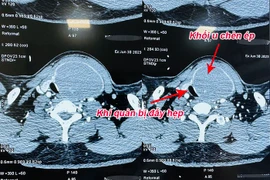

Người bệnh bị bướu cổ hơn 30 năm với kích thước khối u tuyến giáp lớn, chèn ép, đẩy khí quản cổ sang một bên gây khó thở đã được các bác sỹ Bệnh viện Nhân dân Gia Định phẫu thuật thành công.

Bị u tuyến giáp lành tính to không mổ, đến khi nuốt vướng mới đến lại bệnh viện thì u vỡ, chèn ép khí quản, thần kinh thanh quản và thực quản gây nguy hiểm tới tính mạng.

Các bác sĩ Bệnh viện TWQĐ 108 vừa phẫu thuật thành công khối u tuyến giáp khổng lồ với kích thước thùy phải 10x6cm, kích thước thùy trái 12x7cm, phát triển cả lên phía trên và đẩy xuống nền cổ, gây đè hẹp khí quản.